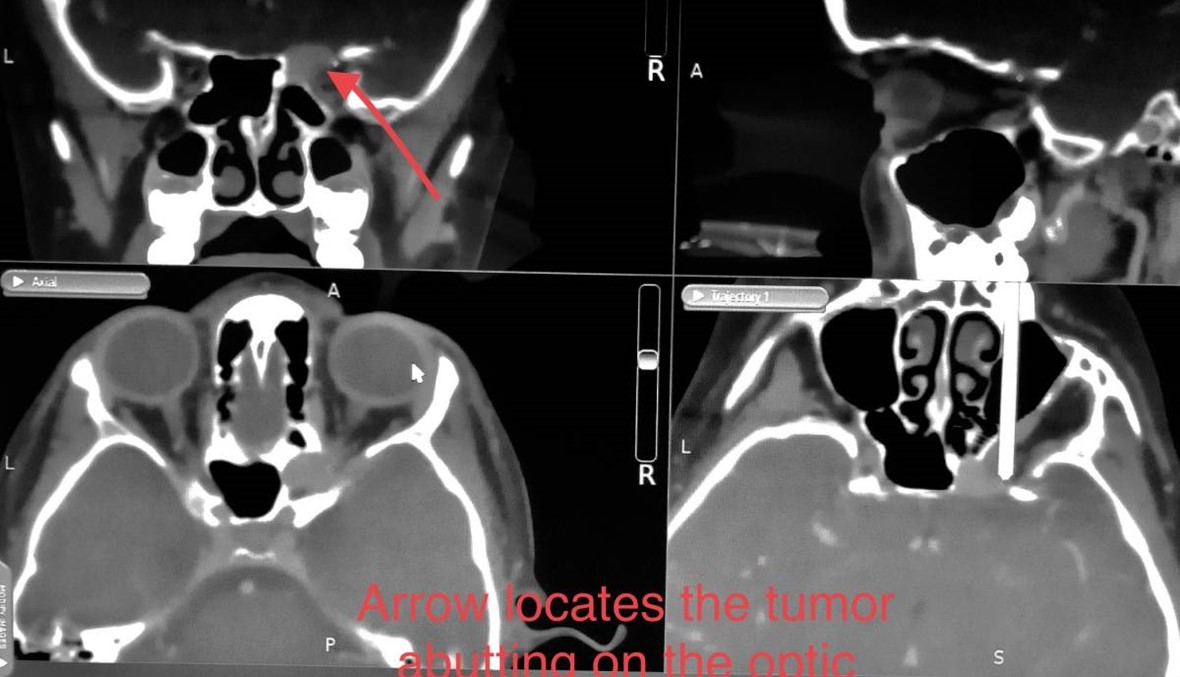

للمرة الأولى في لبنان، أجرت دائرة الجراحة في المركز الطبي في الجامعة الأميركية في بيروت عملية بالمنظار داخل الأنف لاستئصال ورم في العصب البصري ممتدّ حتى الشق المداري الأعلى. وساهم هذا الإجراء المتطوّر في إنقاذ حياة طفلة في الخامسة من عمرها دخلت المركز الطبي مصابة بورم في عصبها البصري امتدّ حتى الشق المداري الأعلى.

وقد أجريت العملية على الطفلة بعد أن ضغط الورم على عصبها البصري، مما أدّى إلى تدهور رؤيتها إلى حد العمى. وبعد أسبوعين من الجراحة، بدأت تتراءى للمريضة ظلال الضوء. ولمعالجة هذا النوع من الأورام، التي تندرج ضمن إطار أورام قاعدة الجمجمة، كان الأطباء يعمدون سابقاً إلى جراحة الدماغ المفتوح (حج القحف).

وتعتبر الجراحة بالمنظار داخل الأنف للعصب البصري تقنية فعّالة وطفيفة التوغّل تتيح استعادة الوظائف البصرية لدى المرضى غير المعرّضين لعمليات انضغاطية مؤلمة من القمة المدارية والعصب البصري.

ويظل توقيت إزالة الضغط حاسماً، لذا على المرضى الخضوع لهذا الإجراء في وقت مبكر من مسار المرض قبل ضمور العصب البصري. واعتمد المنظار الداخلي سابقاً لاستئصال أورام الغدة النخامية، في حين تتيح هذه المقاربة تمديد حدود استئصال الورم من دون اللجوء لفتح الدماغ والجمجمة، مما يؤدي في النهاية إلى التعافي الأسرع ومعدل اعتلال أقل.